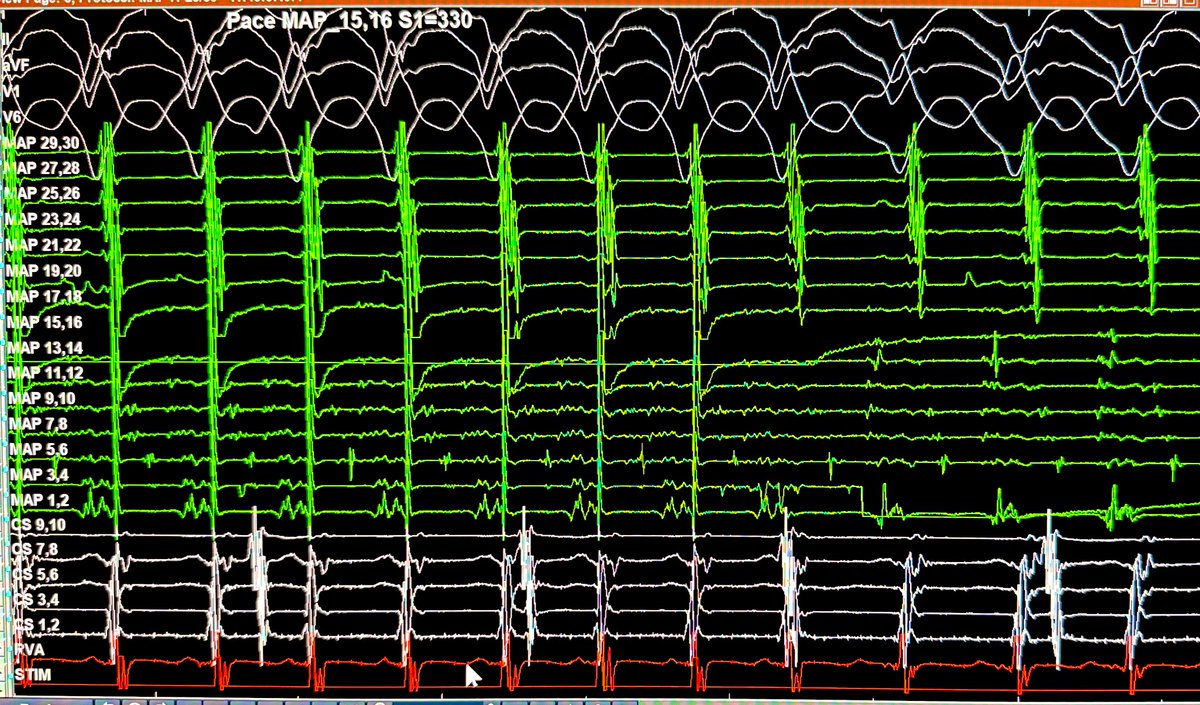

Pace-mapping during idiopathic outflow tract PVC ablation. 10mA output MDI is 0.58 Where did we pace from? Poll below 👇 #EPfellows #Epeeps #AblateVT